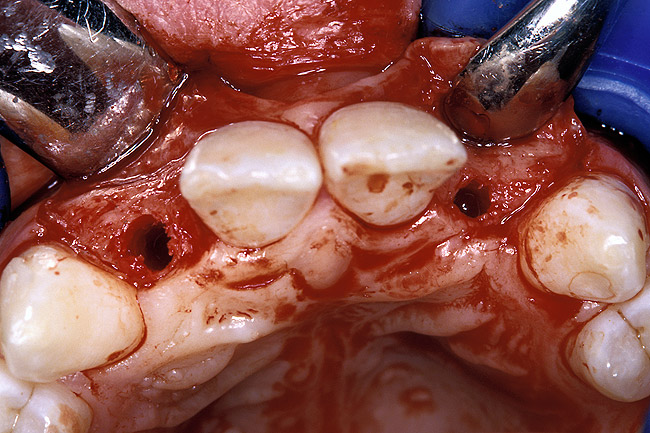

Before the day of surgery, the patient was seen by the orthodontist for the removal of the orthodontic brackets. The patient still was not pleased with the position of the two centrals, and it was determined that this would be addressed after implant placement (Figure 13A). The anatomical variations of the crestal tissue and lack of interdental papilla can be appreciated in the close-up views of the right and left sites (Figure 13B and 13C). There were no surprises on the day of surgery as all of the decisions were made during the planning phase, before the scalpel ever touched the patient. The occlusal view of the CT 3D model revealed the wider alveolar ridge on the right side and thinner crest on the left side (Figure 14A). This was confirmed when the full thickness mucoperiosteal flaps were elevated, and the underyling bone revealed (Figure 14B). The tooth-borne templates were designed to facilitate the drills and drilling sequence specific to the diameters of the predetermined implants (Figure 15A). Each template contained an embedded 5-mm long stainless steel tube, which was approximately 0.2-mm wider than each drill (just wide enough to allow for the drills to rotate freely). Once positioned over the natural teeth, the template was secure and offered precision accuracy in transferring the implant locations from the original software-designed plan, allowing the potential for internal and external irrigation (Figure 15B). The 3.7-mm diameter Tapered Screw-Vent implant drilling sequence requires three drills: pilot, intermediate, and final sizing. Thus, three separate templates were fabricated to a.commodate these sizes. The templates were removed easily and replaced with the next sequential size in less time than it takes to change the drill on the surgical handpiece. After the osteotomies had been.completed, the implants were delivered to the site (Figure 16A and Figure 16B). For this internal hex connection implant, the author r.commends that the flat of the antirotational hex be positioned to the facial for proper orientation of the restorative.components (Figure 17A). Preprepared margins were created from a milled titanium fixture mount transfer post, which was delivered to the implant as support for an immediate transitional restoration. The facial “dot” helped confirm the orientation of the abutment to the facially positioned flat side of the internal hex connection (Figure 17B). Before cementation of the transitional acrylic restorations, a closed-tray, fixture-level impression was made, and a soft-tissue model fabricated.

Figure 14a  The information gained from (A) the 3D model was confirmed when (B) the flaps were elevated.

Figure 14a

Figure 14b  The information gained from (A) the 3D model was confirmed when (B) the flaps were elevated.

Figure 14b